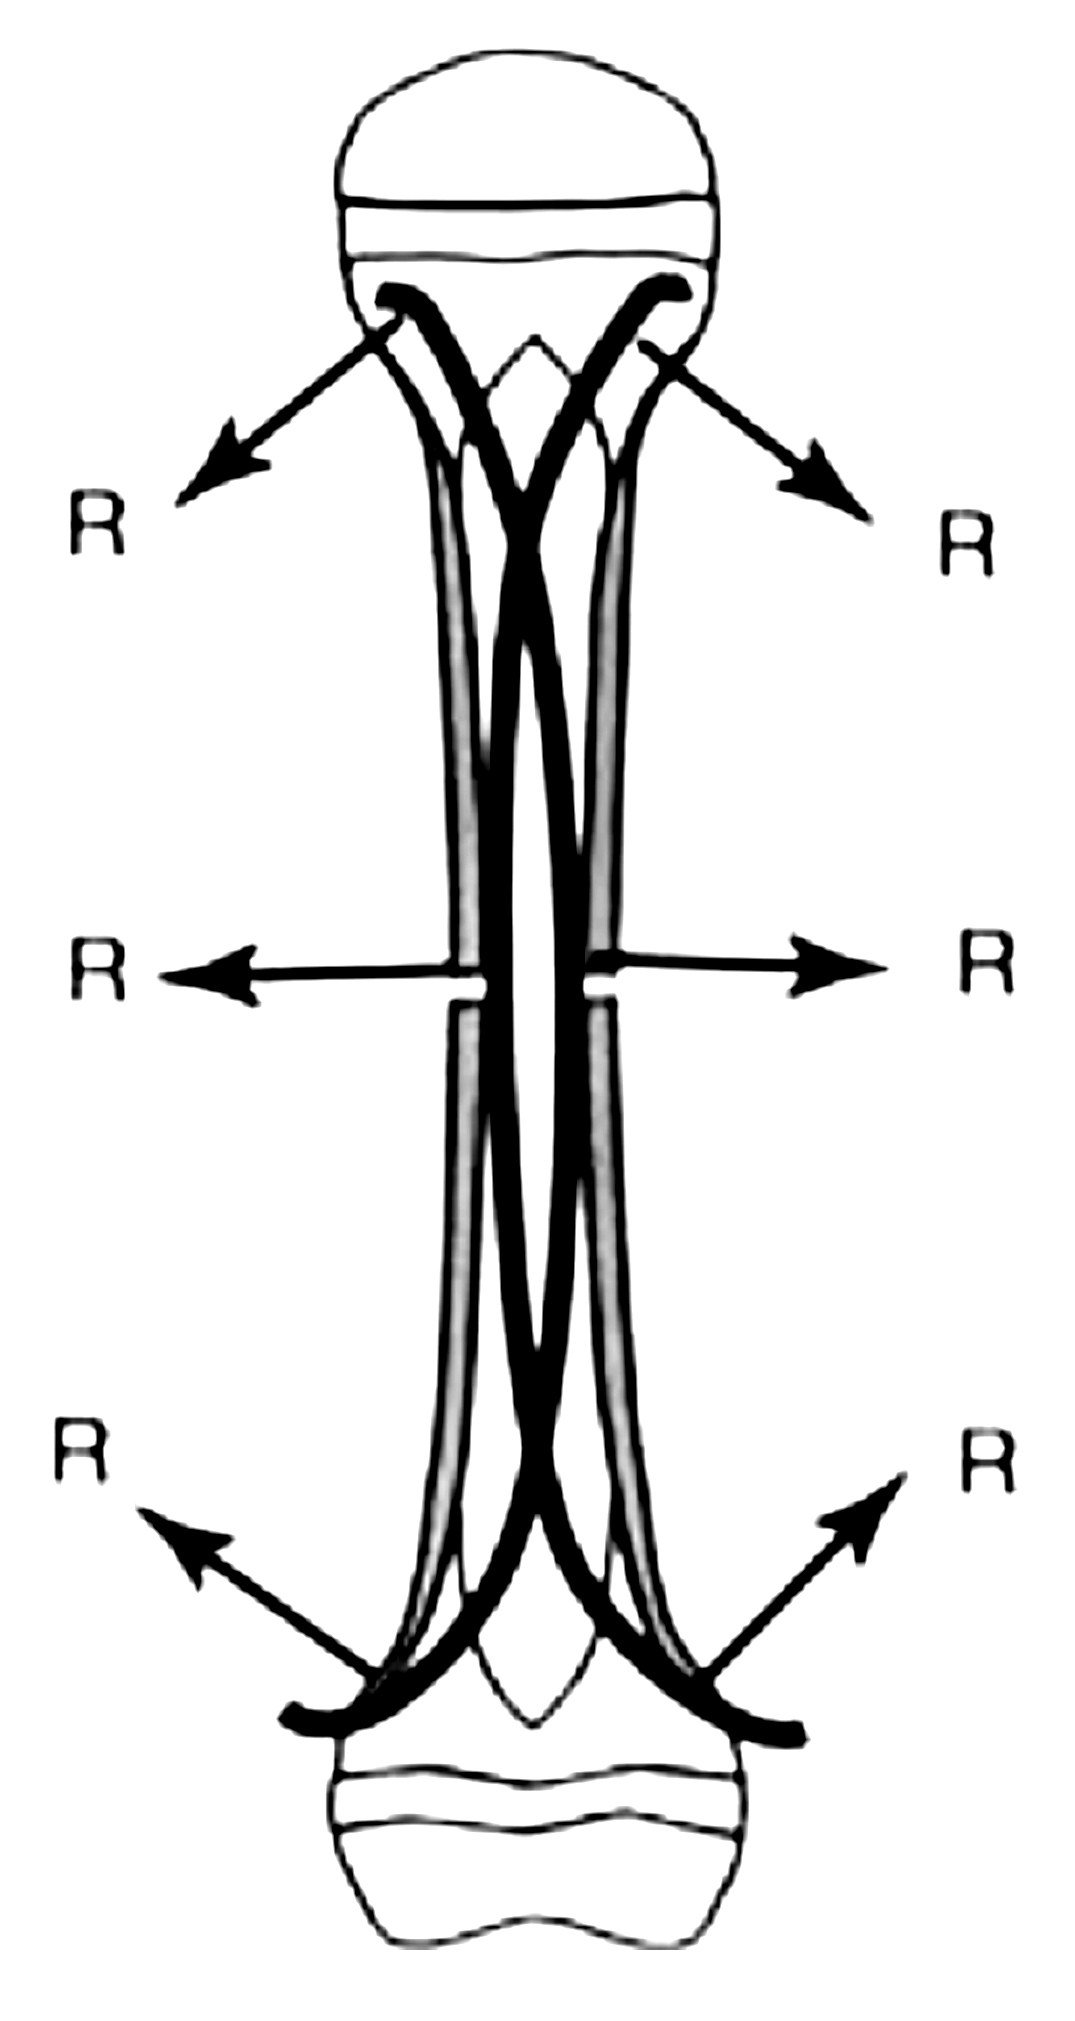

I chiodi vengono pre piegati prima dell’ introduzione con un angolazione di circa 30° (Fig 5) onde determinare il blocco elastico della frattura e i 2 chiodi contrapposti restituiscono le forze in modo dinamico mantenendo la riduzione della frattura e mantenendo il sistema in equilibrio (Fig 6)

Fig 6